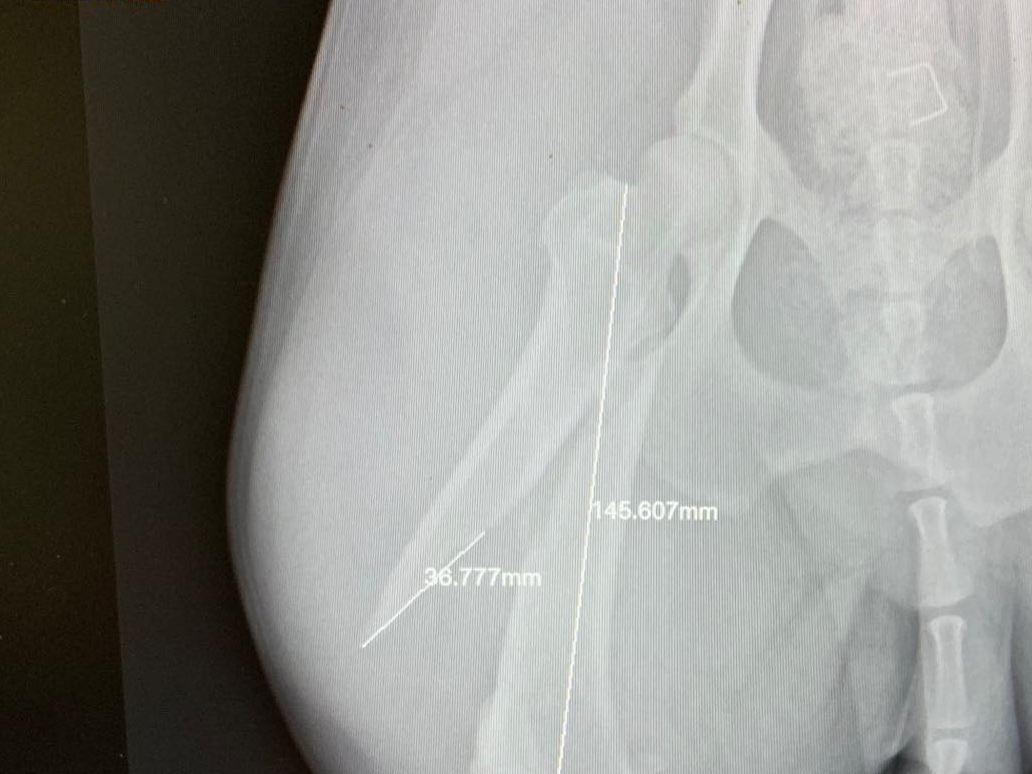

Witam wszystkich. Na forum chciałbym się podzielić naszą historią. Od maja jestem posiadaczem border collie, którego wg. zapewnień hodowcy rodzice są wolni od dysplazji. Niestety w wieku ok. 7 msc zauważyliśmy, że jest problem z chodzeniem, widać taki zajęczę skoki tylnych łapek. Udaliśmy się do kliniki w Poznaniu gdzie lekarz na pierwszy rzut oka stwierdził dysplazję, niestety potwierdziliśmy to badaniem RTG (załączam zdjęcia). Okazało się, że jest to już ciężka dysplazja typu D. Po początkowym szoku chcieliśmy działać żeby jakoś to naprawić. Weterynarz, który wykonał RTG zaproponował metodę resekcji obu głowek- terapia dosyć drastyczna i nieodwracalna(koszt ok. 1700zł za jedną nogę). Stwierdziliśmy, że poszukamy informacji i pomocy u innych lekarzy. Dwóch z trzech stwierdziło, że resekcja to zły pomysł a pies będzie po niej inwalidą. Jeden z weterynarzy polecił wg. niego najlepszą w Europie klinikę w Czechach ABvet, ok. 400km od nas ale czego się nie robi dla kochanego pupila. Po kontakcie mailowym (zero problemów z językiem) i przesłaniu RTG umówiliśmy się na wizytę. Na miejscu lekarz stwierdził, że pies ma tragiczne biodra, ale na szczęście dla niego w wieku 8 msc można jeszcze zrobić podwójną osteotomię obu stawów. Na informację co zaproponowali inni lekarze tj. resekcję powiedział, że nigdy w życiu nie zrobiłby tego takiemu młodemu psu i dla niego byłoby to inwalidztwo. Dodatkowym atutem za osteotomią jest to, że nie jest bardzo wyrośnięty i waży 16kg. Lekarz powiedział, że mamy 2 dni na zastanowienie bo w tym przypadku każdy dzień się liczy. Koszt operacji oszacował na 3tys za jedną nogę. Stwierdziliśmy, że jak się wzięło psa to trzeba też wziąć za to odpowiedzialność i dać mu bezbolesne życie. Doktor powiedział, że nie ma terminów na msc. do przodu, jednak ten niecierpiący zwłoki przypadek gdzieś "wciśnie". Po tygodniu miała mieć miejsce pierwsza operacja tj. 4 grudnia 2018r. Pieska zawieźliśmy na 8 rano, zostawiliśmy go w klinice, poinformowano nas, że pies po operacji zostanie jeszcze ok 2-3 dni. Niestety z przyczyn technicznych operacja przesunęła się o jeden dzień. 7 grudnia dostaliśmy informację, że piesek jest gotowy do odbioru. Lekarz przekazał nam dobre wiadomości, że wszystko się udało a następna operacja będzie 20 grudnia. Ciąg dalszy nastąpi. Cywil jest po drugiej operacji, stan biodra był tragiczny, jednak udało się poprawić panewkę i jej kątowanie. Pierwsza rana się zagoiła bardzo szybko. Z drugą jest trochę komplikacji, ponieważ zaczął się zbierać płyn i trzeba było go spuścić. Pies dochodzi do siebie i zaczyna coraz bardziej obciążać lewą nogę. Jeśli ktoś chciałby jakieś szczegółowe i dodatkowe informację to proszę o kontakt. Zdjęcie RTG po dwóch operacjach: https://zapodaj.net/50ff53cd830e2.jpg.html